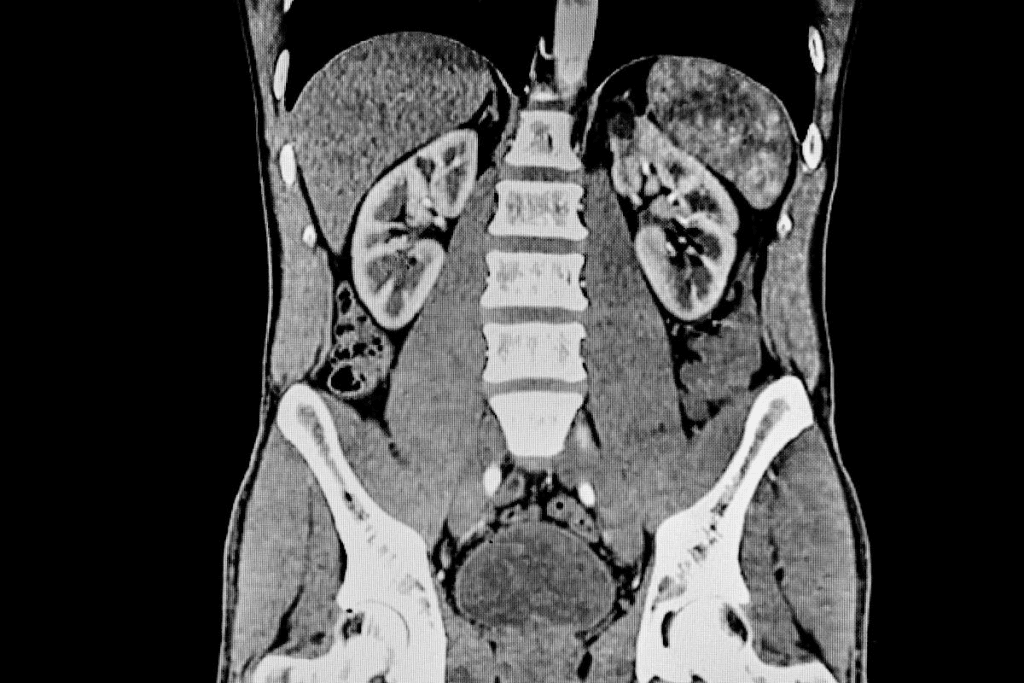

A CT urogram is a high-tech imaging method. It helps doctors see the urinary tract clearly. It’s great for checking the kidneys, ureters, and bladder.

A CT urogram, or computed tomography urography, uses X-rays and dye to see the urinary system. The dye goes through the body and lights up the urinary tract. This makes it easy to spot problems.

The dye is key because it shows the urinary tract. It helps find stones, tumors, or other issues. CT urograms are very good at finding these problems, with a high success rate.

The CT urogram takes pictures at different times. This lets doctors see the urinary tract in detail. It shows how it works and looks at different stages.

First, it looks for stones or calcifications. Then, it shows the kidneys, collecting system, and ureters with dye. This helps find many urinary tract problems.

Standard CT scans show the body’s inside, but CT urograms focus on the urinary system. They use a special protocol with dye and multiple phases. This gives a closer look at the urinary tract.